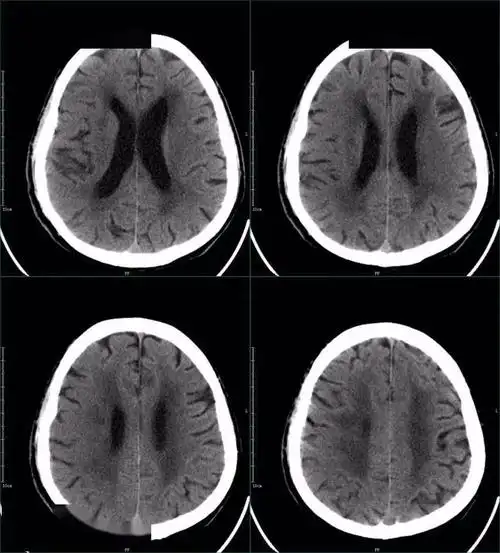

67超急性期大面积脑梗死ct平扫表现